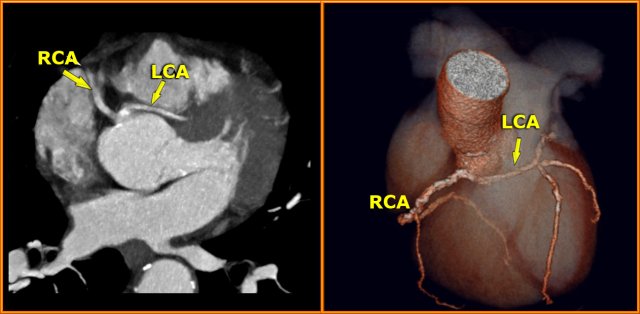

Left Coronary Artery (LCA)

The left coronary artery (LCA) is also known as the left main.

The LCA arises from the left coronary cusp.

The LCA divides almost immediately into the circumflex artery (Cx) and left anterior descending artery (LAD).

On the left an axial CT-image.

The LCA travels between the right ventricle outflow tract anteriorly and the left atrium posteriorly and divides into LAD and Cx.

On the image on the left we see the left main artery dividing into

- Cx with obtuse marginal branch (OM)

- LAD with diagonal branches (DB)

On volume rendered images the left atrial appendage needs to be removed to get a good look on the LCA.

In 15% of cases a third branch arises in between the LAD and the Cx, known as the ramus intermedius or intermediate branch.

This intermediate branche behaves as a diagonal branch of the Cx.

Right Coronary Artery (RCA)

The right coronary artery arises from the anterior sinus of Valsalva and courses through the right atrioventricular (AV) groove between the right artium and right ventricle to the inferior part of the septum.